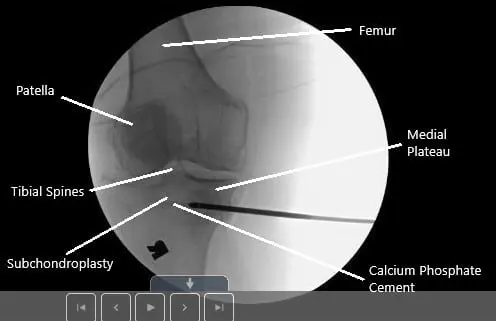

MRI of the right knee in sagittal section showing tear of the medial meniscus.

MRI of the right knee in sagittal section showing tear of the medial meniscus

MRI of the right knee suggested a complex tear of the posterior horn of the medial meniscus, tibial subchondral stress fracture, and severe patellofemoral arthrosis. Due to the failure of the conservative management, the patient was advised surgical management. Risks, benefits, and potential complications were all discussed at length with the patient. The patients agreed to go ahead with the procedure.